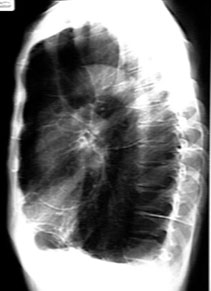

Each tissue reacts to injury in a predictable fashion. Multiple etiology can evoke a similar pathological reaction. Let us review the pathological process that can occur in the lung following lung injury. Lung injury can be either generalized or localized. The consequence of lung injury could either lead to a liquid or increased air density in CXR. There are radiological signs for each of the pathological process.